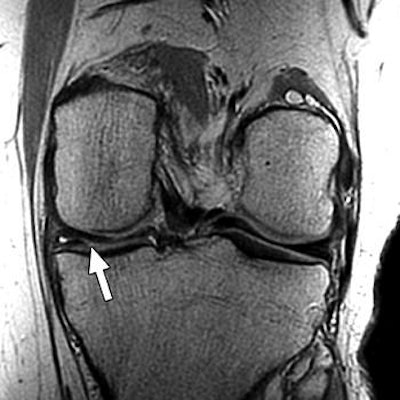

| Above, 27-year-old man with meniscal tear. Coronal 2D fast spin-echo (FSE) image (TR/TEeff, 4,000/38) shows tear (arrow). Middle, coronal 3D FSE extended echo-train acquisition (XETA) image (TR/TEeff, 2,500/38). Tear (arrow) was visible on two images of 2D FSE acquisition and 12 of coronal 3D FSE XETA images. Below, sagittal reformation of 3D FSE XETA dataset shows tear (arrow). |

Imaging at 3 tesla improved the resolution of 3D FSE XETA to 0.6-mm isotropic compared with 0.7-mm isotropic for 1.5-tesla images, the authors stated. In the volunteer with knee pain, 3D FSE XETA and 2D FSE revealed a meniscal tear in the posterior horn of the medial meniscus. Still, on the 3D FSE XETA, the tear was visible on a dozen images in the coronal plane versus two images from the 2D FSE acquisition.